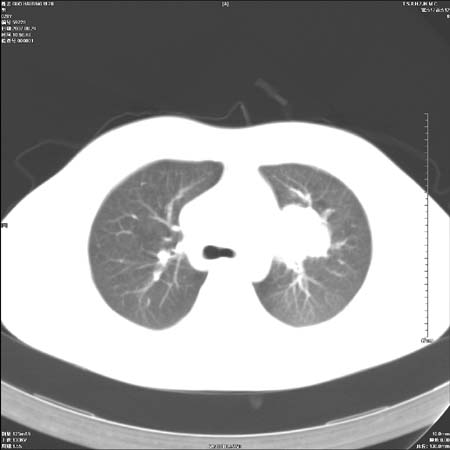

本例倾向周围型肺癌

鉴别:中央型肺癌-肿块那么明显一般合并节段肺不张或阻塞性炎症。

本例肿块边缘外侧可见左上叶各段支气管。

左侧肺门区见一块状病灶可见分叶,纵隔内及左肺门见肿大淋巴结,应该是周围型肺癌而不是中心型肺癌,原因有以下2点,1未见阻塞肺气肿和阻塞性炎症,这么大肿块如果是中心型肺癌就是未分化型或小细胞型肺癌不出现阻塞性肺不张也应该有阻塞炎症或阻塞性肺气肿,2如果是中心型肺癌临床出现最早的症状是咳嗽(此时可无任何异常影象),而此人这么大肿块只有背部隐痛是体检才发现无法解释.

直接下肺癌诊断还太早,病灶较大,估计5cm以上,但阻塞性改变及对临近纵隔及支气管侵犯不明显,密度较均匀,弓旁见一单个淋巴结,需要排除炎症性肿块及腺瘤,平滑肌瘤等。